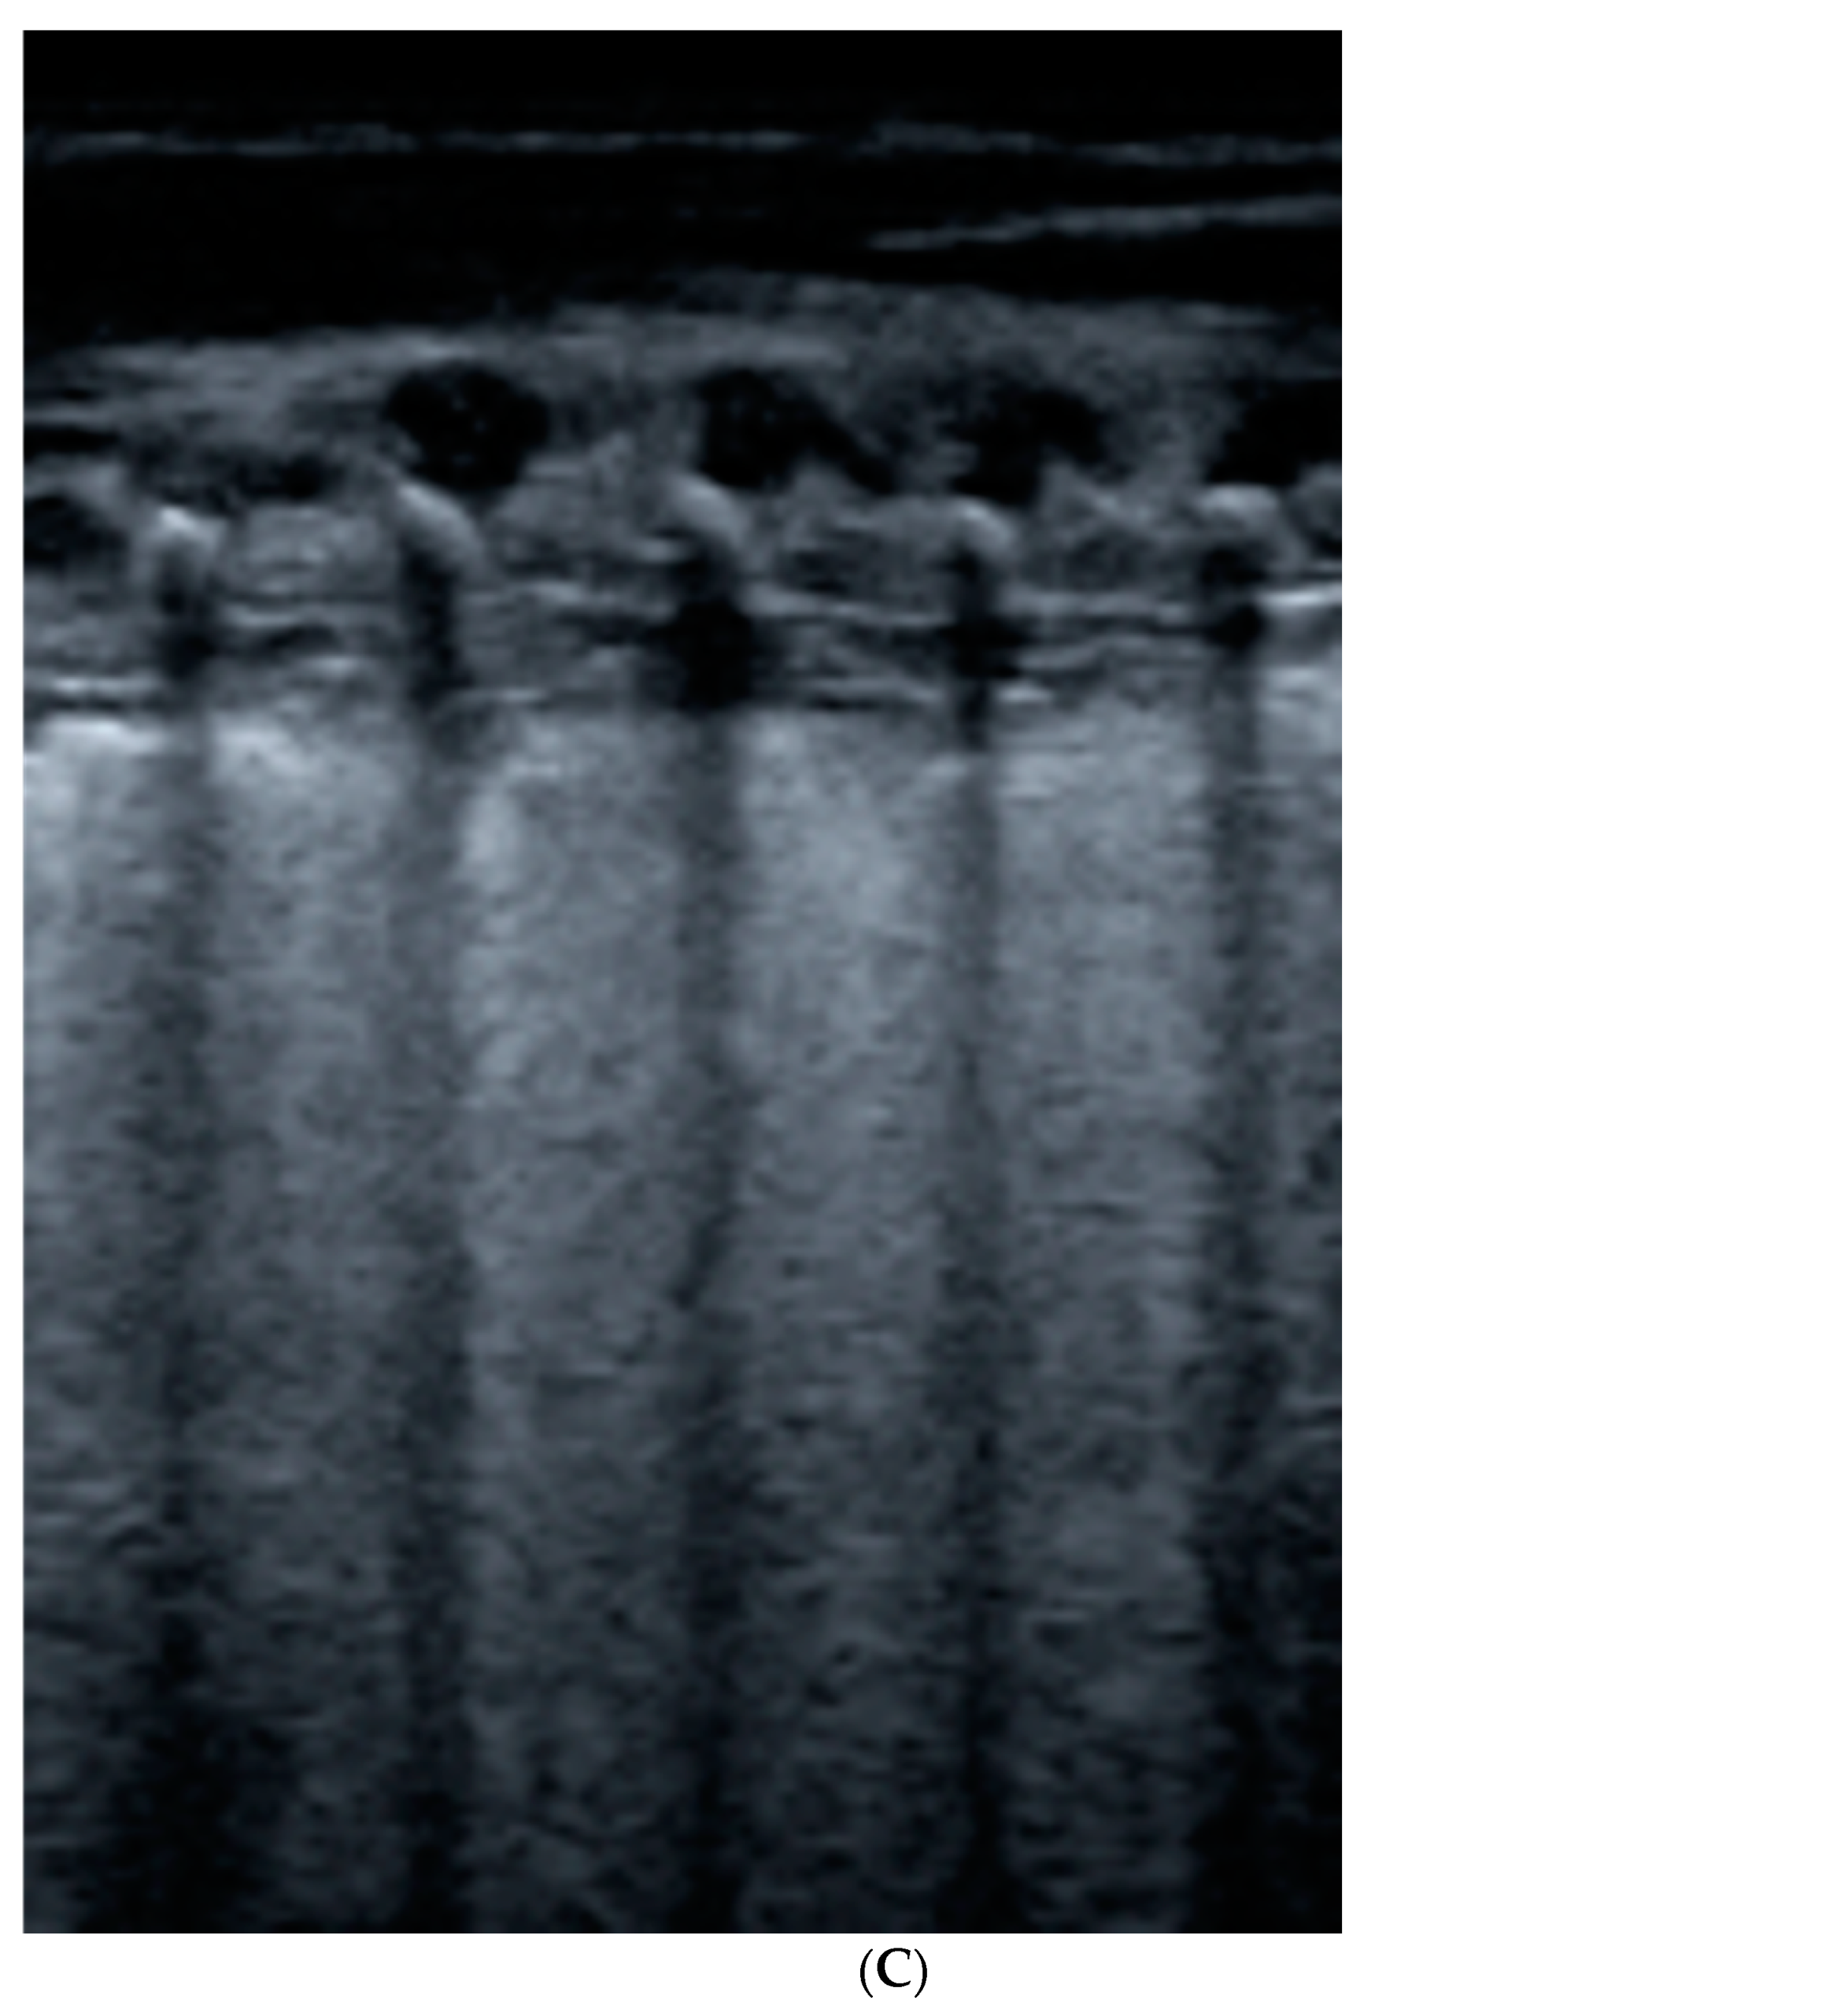

- Seashore sign (lateral): echogenic pleural line divides the image in the motionless part represented by horizontal lines (sea waves) and the part below that appear granular (sand) as the normal to-and-from motion of the lung is reflected over that area (normal lung sliding).

- Barcode sign (central): absence of a dynamic image, substituted by a static posterior acoustic shadowing (horizontal lines).